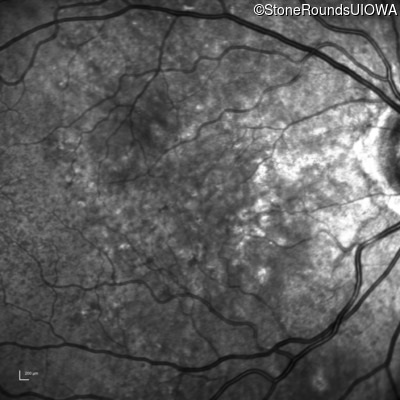

Pseudoxanthoma Elasticum (IID2)

Age at visit: 58 years

Diagnosis & molecular findings

Disease Gene Allele 1 variant(s) Allele 2 variant(s) Inheritance mode

Pseudoxanthoma Elasticum ABCC6 Gly928 del4tacGGCA IVS21+1 G>T AR